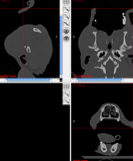

Im Bild sieht man die CT-Aufnahme eines intubierten Windhundes.

DICOM-Viewer

Die Planungssoftware erlaubt es die CR/MRT Bilder in drei Ansichten am Bildschirm darzustellen und durchzublättern.